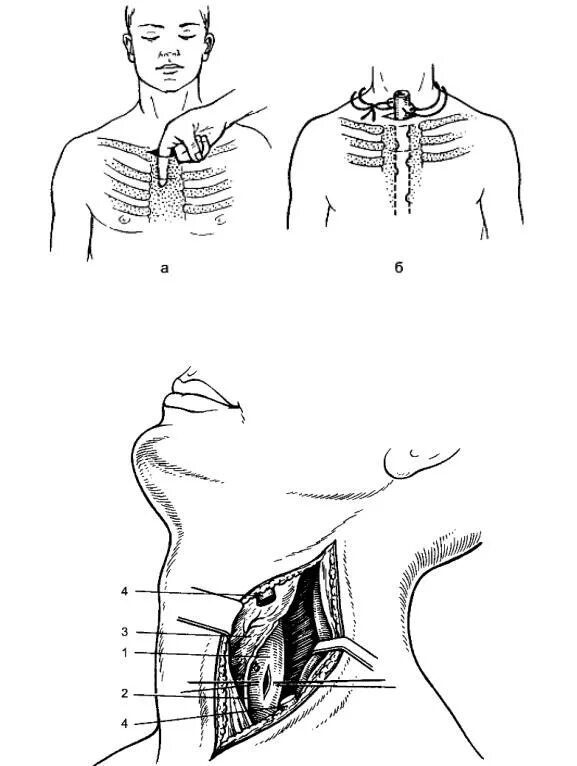

Медиастинит причины